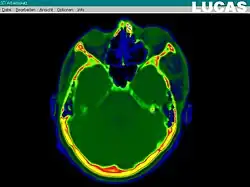

The most important component for CAS is the development of an accurate model of the patient. This can be conducted through a number of medical imaging technologies including CT, MRI, x-rays, ultrasound plus many more. For the generation of this model, the anatomical region to be operated has to be scanned and uploaded into the computer system. It is possible to employ a number of scanning methods, with the datasets combined through data fusion techniques. The final objective is the creation of a 3D dataset that reproduces the exact geometrical situation of the normal and pathological tissues and structures of that region. Of the available scanning methods, the CT is preferred,[1] because MRI data sets are known to have volumetric deformations that may lead to inaccuracies. An example data set can include the collection of data compiled with 180 CT slices, that are 1 mm apart, each having 512 by 512 pixels. The contrasts of the 3D dataset (with its tens of millions of pixels) provide the detail of soft vs hard tissue structures, and thus allow a computer to differentiate, and visually separate for a human, the different tissues and structures. The image data taken from a patient will often include intentional landmark features, in order to be able to later realign the virtual dataset against the actual patient during surgery. See patient registration.

Image analysis involves the manipulation of the patients 3D model to extract relevant information from the data. Using the differing contrast levels of the different tissues within the imagery, as examples, a model can be changed to show just hard structures such as bone, or view the flow of arteries and veins through the brain.